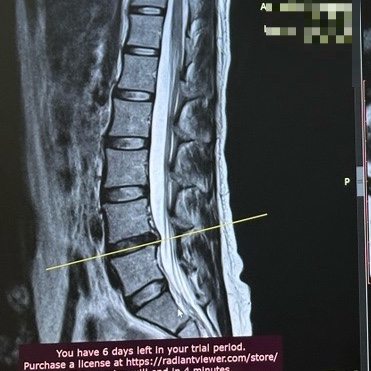

육아중 허리디스크 파열로 입원 후 보존치료 시작

요새 블로그에 뜸했던 이유 : 허리디스크가 터졌다.. 6월 중순 아기를 내려놓다가 허리가 시큰했었다. 그날...